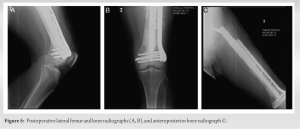

The patient is placed in lateral decubitus position with standard skin cleaning and preparation with chlorhexidine and iodide solution and iodide surgical drape. A hip posterolateral extended approach to the femoral diaphysis is performed to expose the entire endoprosthesis. The endoprosthesis is removed and resection of a segment of femoral diaphysis is done. This resection was performed to remove all devitalized bone tissue. Intraoperatively, the vitality and bleeding of the bone is verified, any segment that shows that it is in poor condition must be resected. Next distal femur preparation is performed with femoral reamers. Retrograded cementation and insertion of the new femoral cemented stem of greater diameter; coupling and fixing the rest of the endoprosthesis. Afterward dissection and exposure of the distal femur application of condylar support plate by a MIPO technique or using a provisional fixation with two Kirschner nails. The position is verified under image intensifier. Definitely, fixation was done with 5 distal locked screws and 2 periprosthetic screws on the distal diaphysis of the femur. Application of a cement mantle to achieve an adequate interface between the endoprosthesis and the plate and that the holes of the plate become full with cement is an essential step that allows better stability (Figs. 2 and 3). Finally, proximal fixation of the plate is performed with surgical cables which are tightened and closed. Inpatient management and rehabilitation follow during the first 3 days, allowing immediate mobilization of adjacent joints and weight-bearing. Follow-up was carried out until the 4th post-operative year. No patient required revision or presented radiological signs of loosening.

Retrograde cementing technique was performed, which is widely known since Barrack et al. proved in 1992 that it decreases the loosening rate significantly [8]. Recently, in 2019, Phelon et al. reported that cemented femoral endoprosthesis is a versatile option that allows immediate full weight-bearing. Augmenting the construct with a condylar plate fixed with periprosthetic screws and surgical cables is an option that ensures more rigidity in primary stability. Literature shows its use, especially in distal femur periprosthetic fractures [9]. Song et al. reported that fixation of periprosthetic fractures with locking plates provided satisfactory results with a low risk of complications and additional surgeries [10]. In addition, a cement mantle was built between the endoprosthesis to achieve an adequate interface between the endoprosthesis and the plate and avoid metallosis or corrosion between the different metals. Using the following keywords, a literature search was performed on PUBMED and EMBASE: Proximal femur endoprosthesis, aseptic loosening, Augmentation, condylar plate, polymethylmethacrylate. We found no articles reporting this technique in aseptic loosening of proximal femur endoprosthesis. Different therapeutic options have been studied for endoprosthesis aseptic loosening including the use of bone allografts, especially for large femoral bony defects [11], use of wire mesh and cerclage wiring with impaction bone allograft into which the femoral stem is implanted [12], and total femur prosthesis, which provides good functional results but high rates of complications such as infection (13–18%), dislocation (6–10%), and material failure (3–6%) [13,14]. In the case of periprosthetic infection, the approach must ensure infection control in the first instance to ensure better results. The revision could be performed in one or two stages with reinfection rates of up to 37% [15]. The clinical relevance of our technique is that it allows early mobilization and weight-bearing, allowing rapid rehabilitation and return to the previous functionality. Our series of patients shows good clinical results on the immediate post-operative period, 2 weeks and 2 months and 4 years follow-up, especially with complete resolution of thigh pain and no radiological signs of development of new loosening of the endoprosthesis (Fig. 4 and 5).